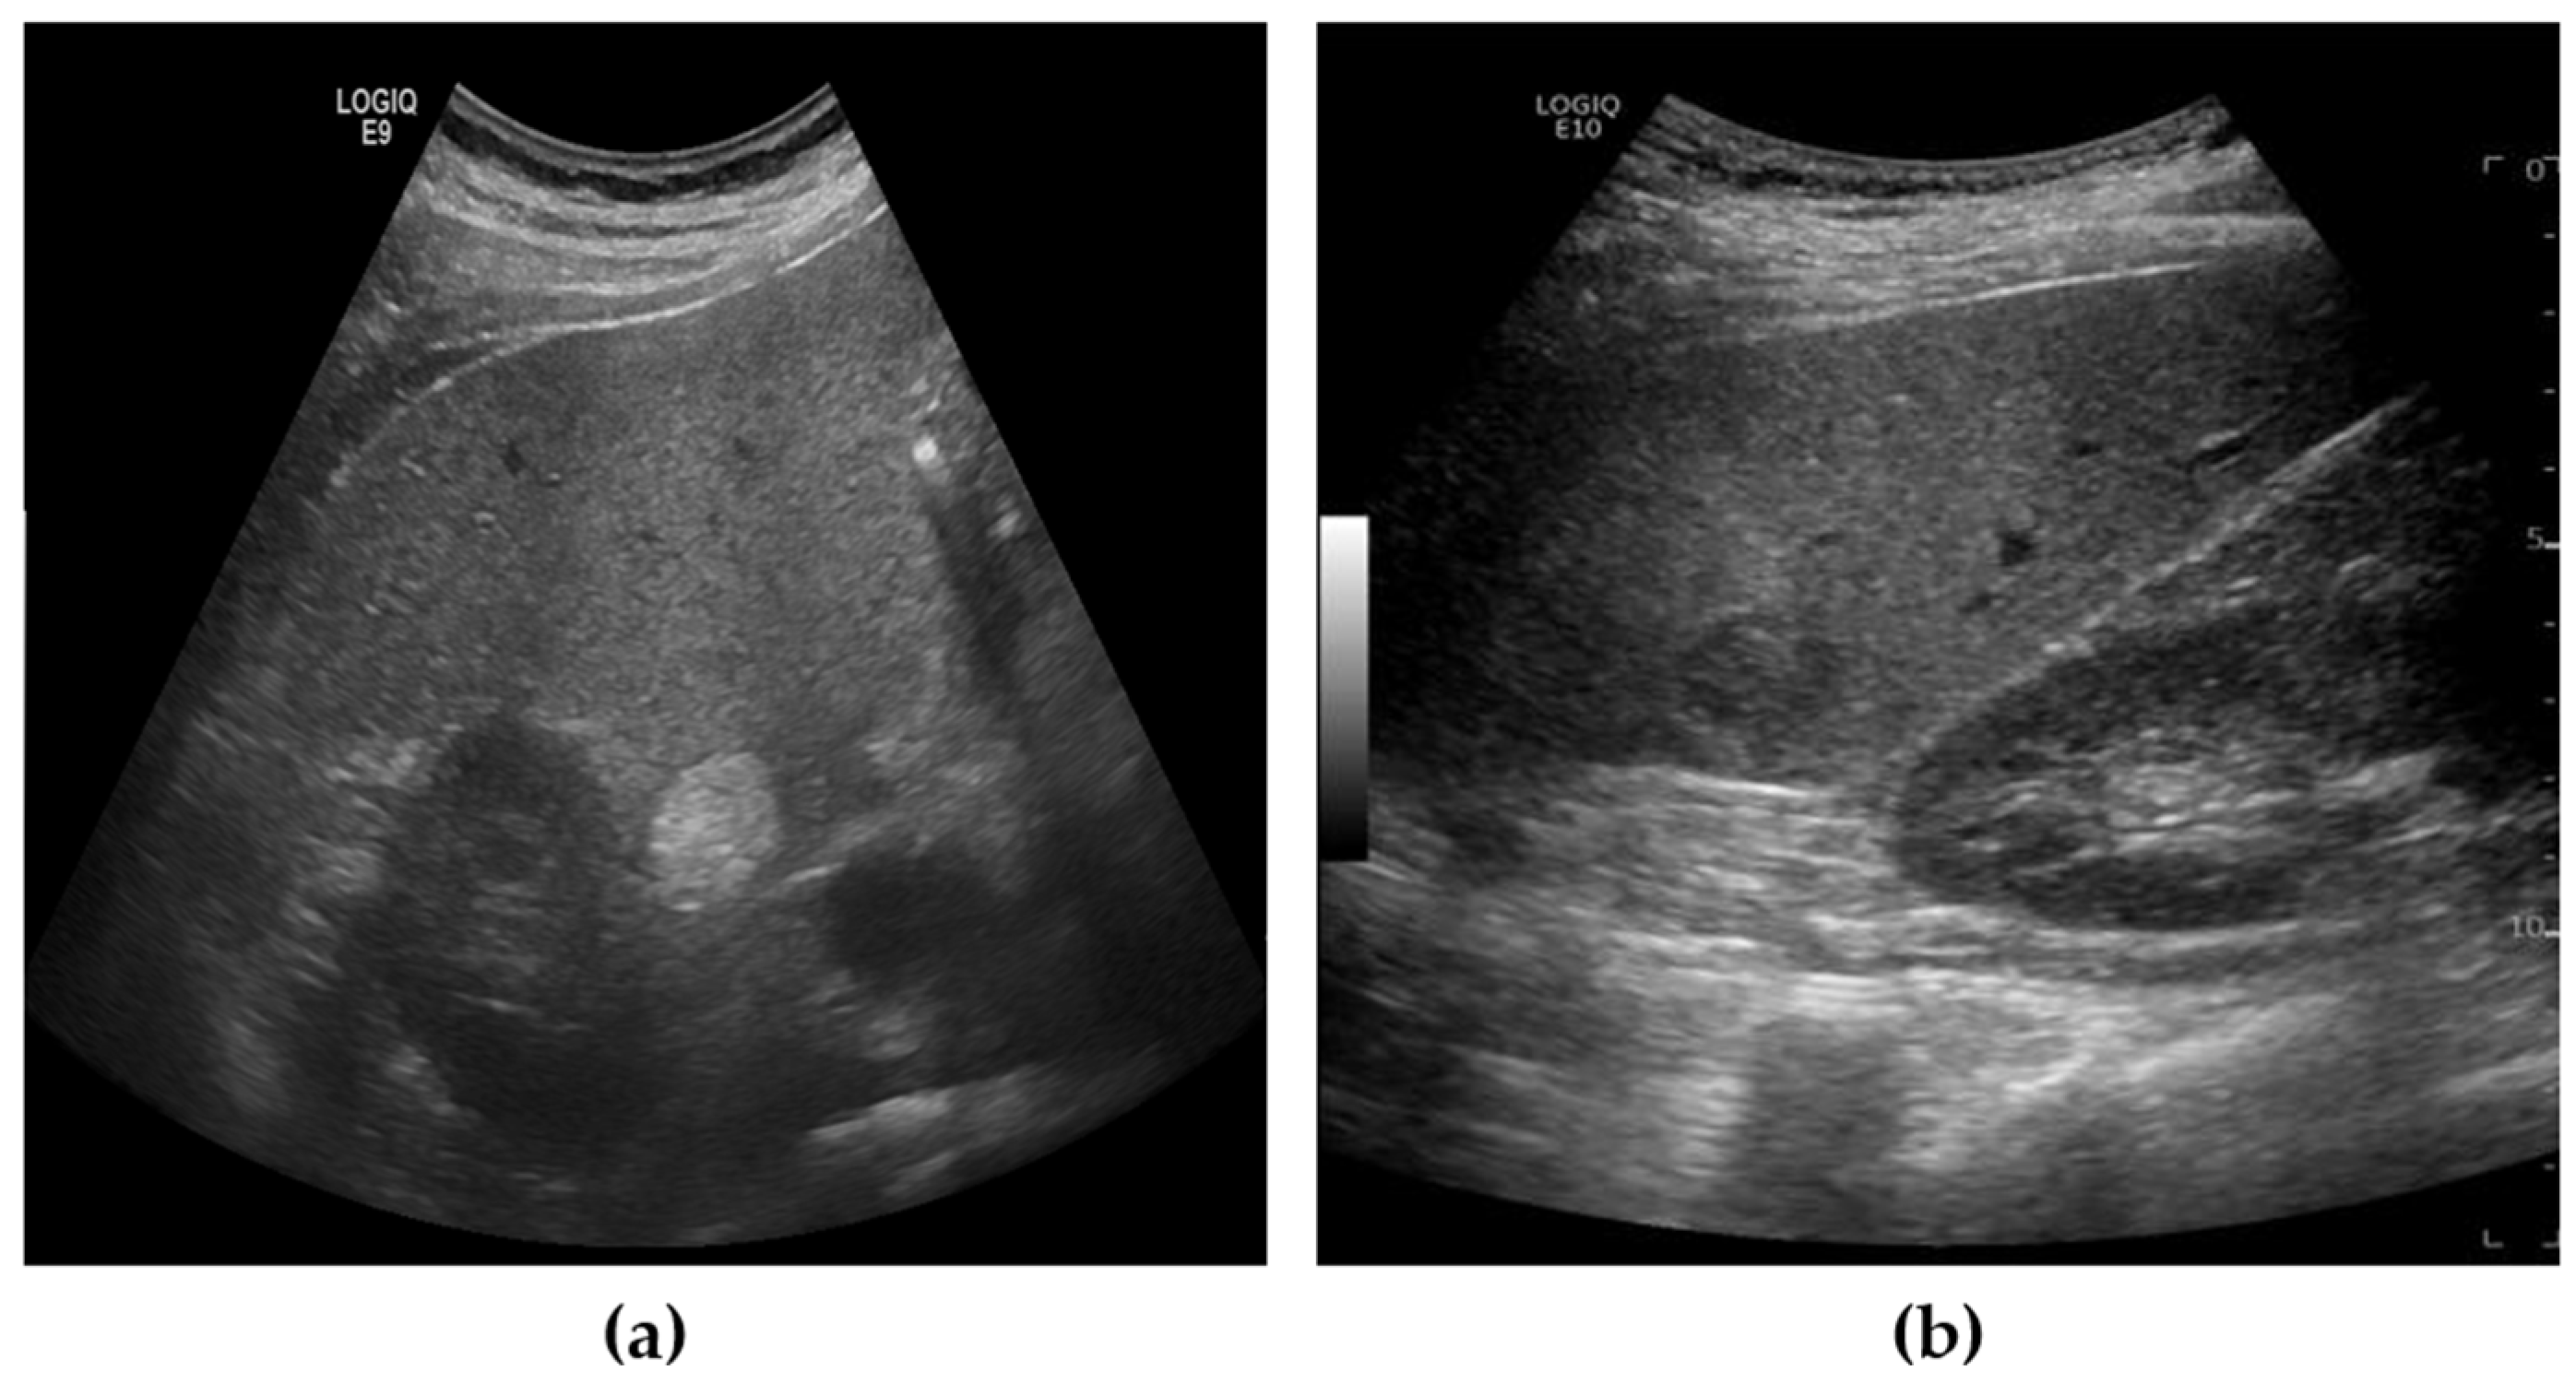

The liver US images used in this study were acquired using the Siemens ACUSON Sequoia 512 system (Siemens Healthineers, Erlangen, Germany), which operates at a frequency range of 3 to6 MHz, with 256 gray levels and a maximum depth of 36 cm. These images were collected under data use agreements and approved by the Institutional Review Board (IRB) of SMC, one of South Korea’s leading hospitals (SMC-2020-10-178-002). The dataset was annotated with two categories: benign and malignant. Since accurate diagnosis using only US images is challenging, the final labels were determined by SMC’s expert physicians after completing all necessary diagnostic procedures, including CT, MRI, and biopsy. The annotation for each patient’s US images was based on these comprehensive findings. Given the goal of our study to develop a screening tool, lesions were categorized simply into benign or malignant, rather than employing more granular labeling. Figure 1 provides examples of benign and malignant cases from our dataset.

Figure 1. Example of US images from dataset. (a) Benign, (b) Malignant.